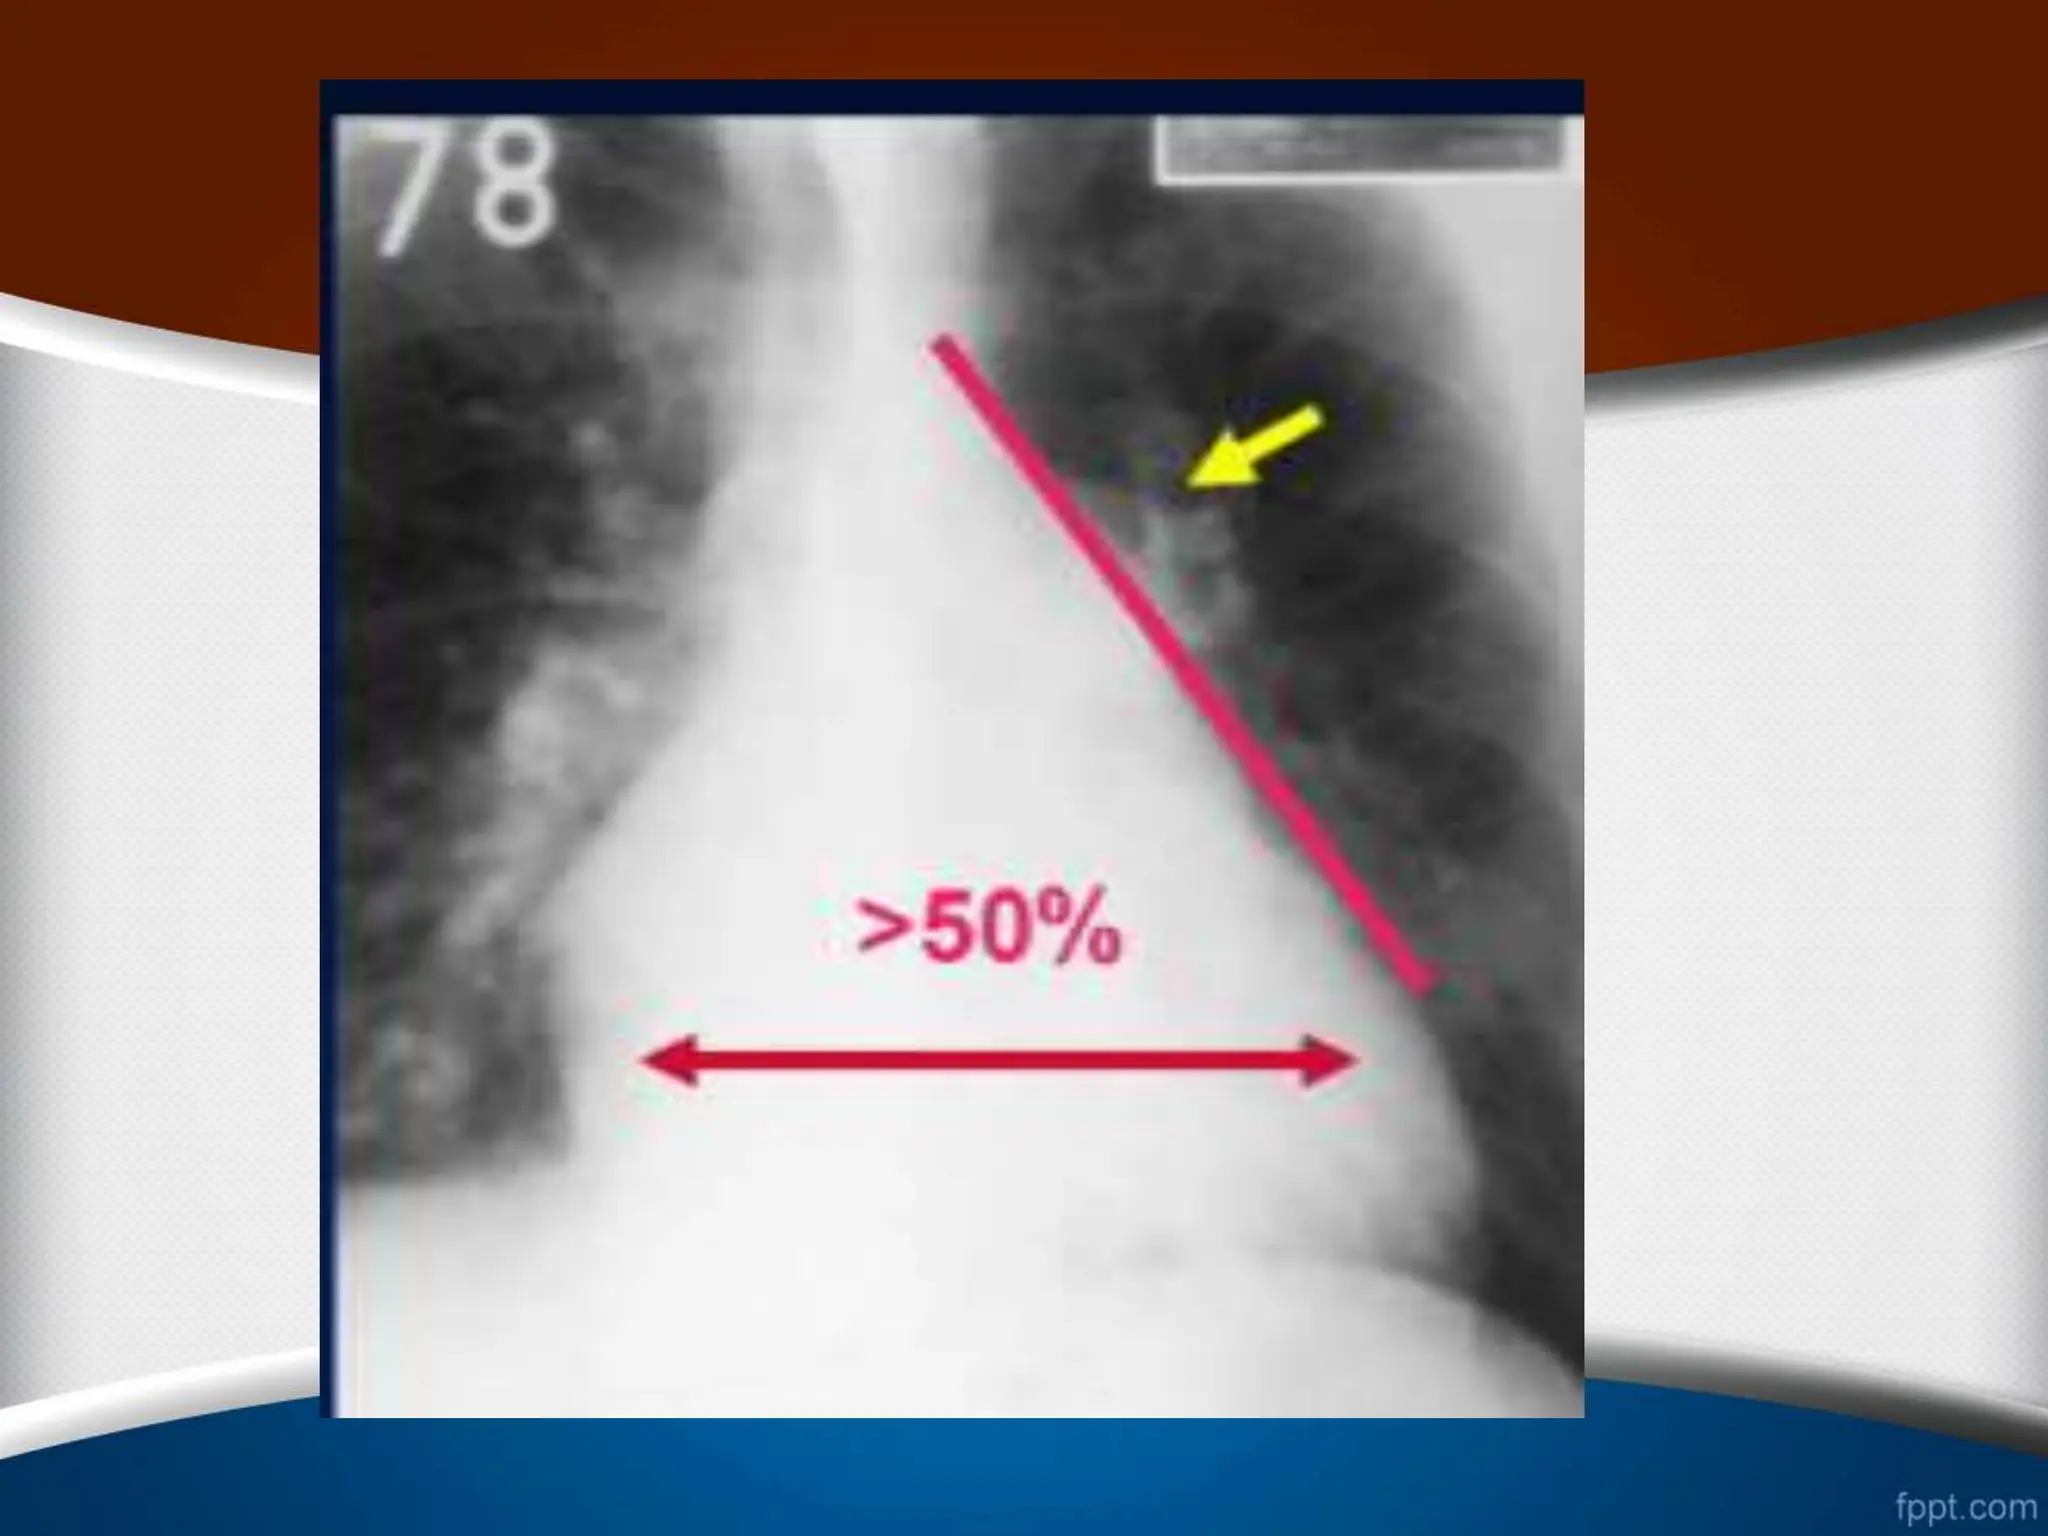

.4

‫می‬ ‫تشکیل‬ ‫را‬ ‫توراکس‬ ‫همی‬ ‫سوم‬ ‫یک‬ ‫از‬ ‫بیشتر‬ ‫راست‬ ‫دهلیز‬

‫دهد‬

.

>25%

>1/3